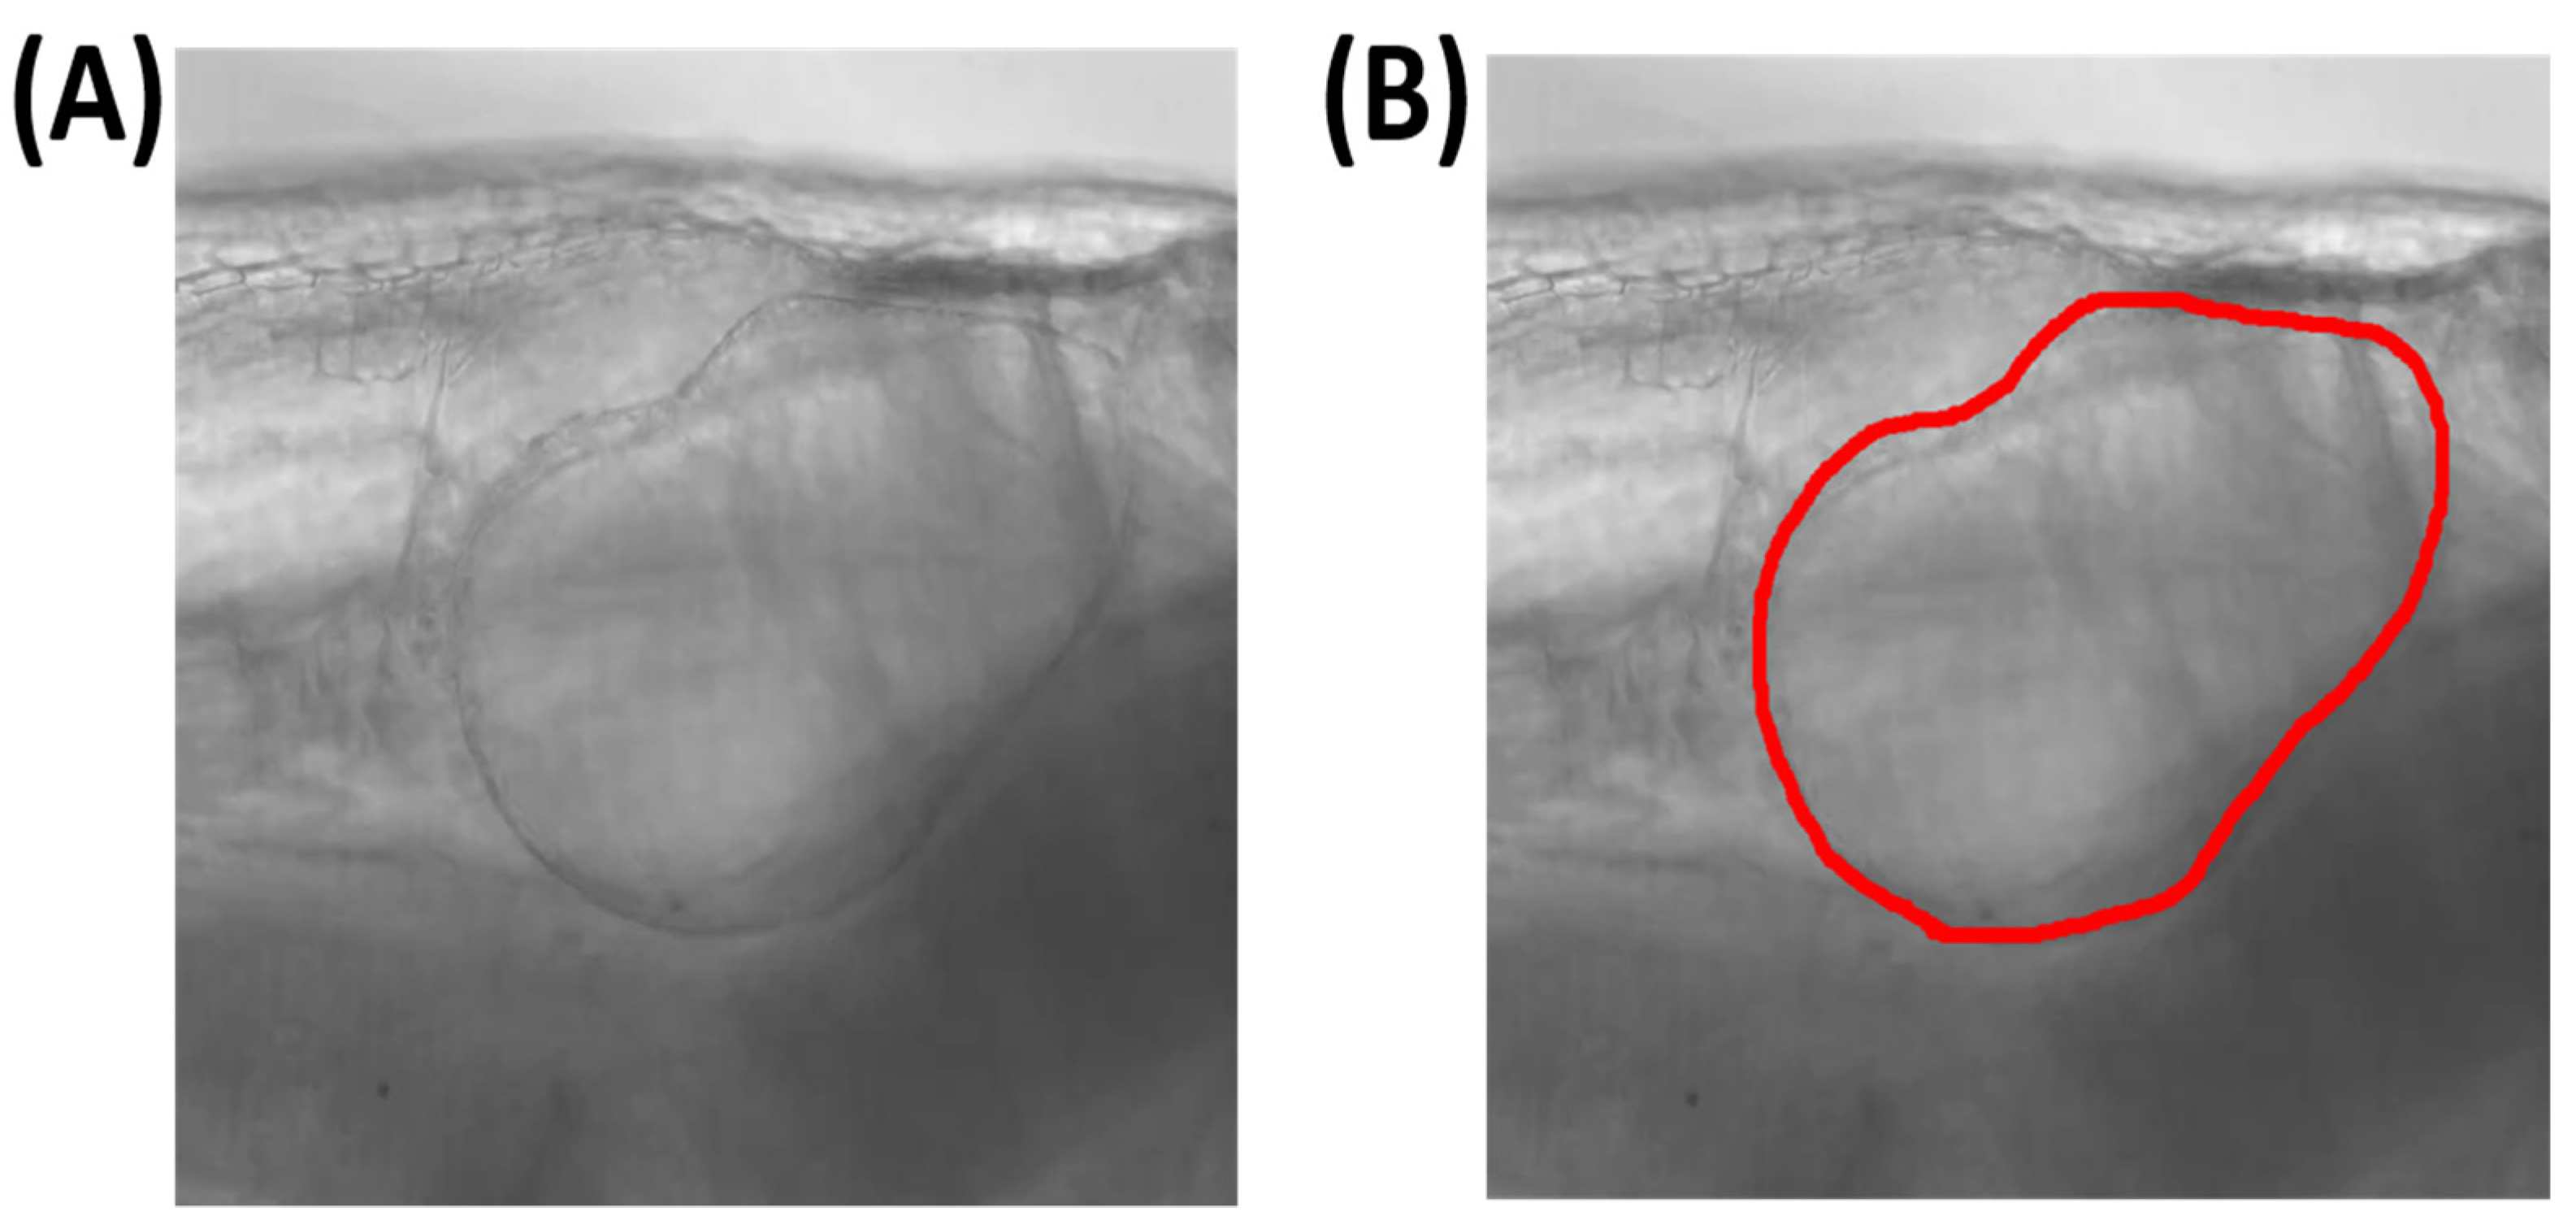

3.1. Overview of Experimental Design and Training Dataset Preparation

3.2. Training and Validation Performance

3.3. Testing Process